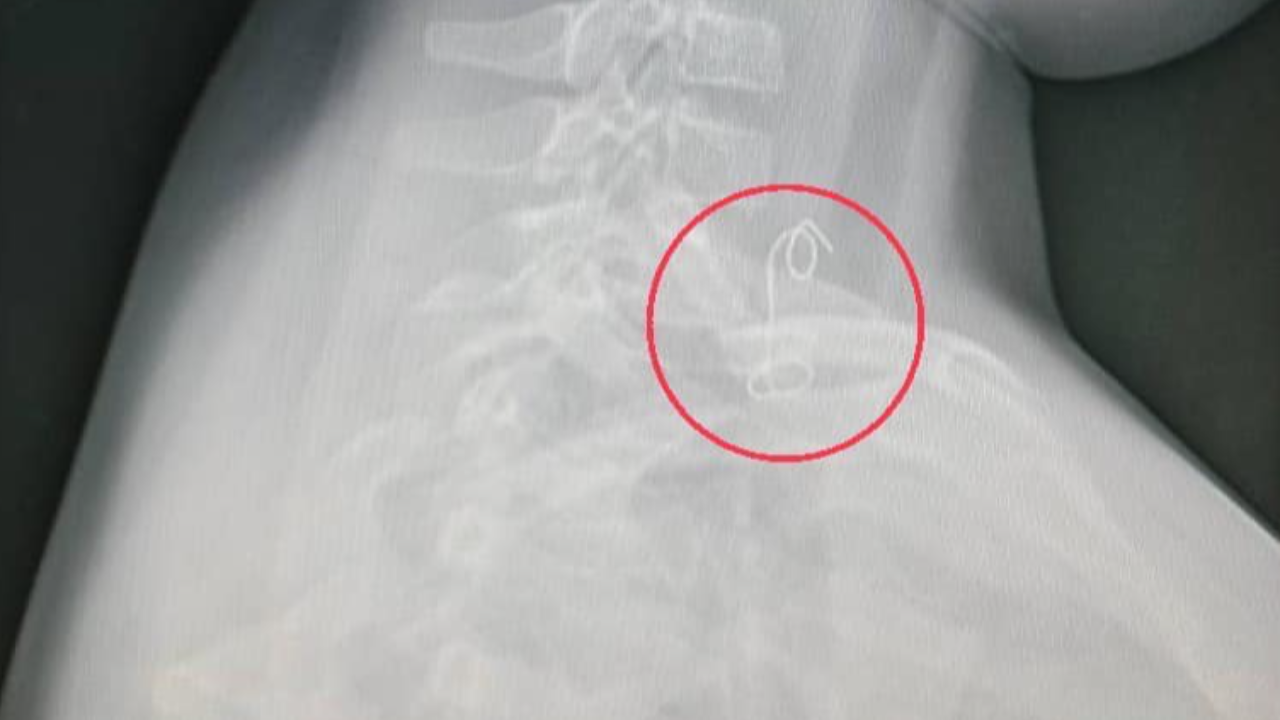

แพทย์ห้องฉุกเฉินส่งเอกซเรย์ เห็นเป็นวัตถุคล้ายขดลวดติดอยู่บริเวณส่วนต้นหลอดอาหาร ปรึกษาแพทย์ผู้เชี่ยวชาญด้านหู คอ จมูก เปิดห้องผ่าตัดด่วน ต้องดมยาสลบวิธีพิเศษ ใส่ท่อช่วยหายใจทางจมูก เพื่อป้องกันไม่ให้สำลักระหว่างผ่าตัด ใช้เครื่องมือส่องกล้องคีบเอาสิ่งแปลกปลอมออกมาได้

สิ่งที่เห็นนอกจากเศษปีกไก่ย่างที่ยังติดค้าง รวมไปถึงลวดมัดไก่ย่าง ยาวประมาณ 8 เซนติเมตร ออกมาด้วยได้สำเร็จ ผู้ป่วยพักฟื้นในโรงพยาบาลฉีดยาต้านเชื้อ 3 วัน ให้กลับบ้านได้อย่างปลอดภัย เตือนภัยใกล้ตัว ให้บุตรหลานกินอาหารไก่ย่างมัดลวดต้องระวังให้ดี.